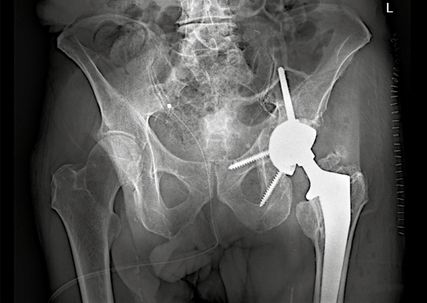

Die PRS-Pfanne zeichnet sich durch ihre massive Bauweise, multiple Schraubenoptionen und die Möglichkeit einer zentralen Ileumschraube aus. Nach Einbringen der Pfanne wird diese korrekt ausgerichtet (Inklination ca. 40–45°, Anteversion ca. 15–20°). Der entscheidende Schritt ist die Platzierung der zentralen Ileumschraube. Dafür wird unter Bildwandlerkontrolle ein Bohrdraht in den supraazetabulären Korridor gesetzt (Abb. 3a u. 3b) und mit dem 6-mm-Bohrer überbohrt. Anschließend wird die Schraube durch das entsprechende Positionsloch der Pfanne in den supraazetabulären Anteil des Iliums eingebracht. Dabei ist auf eine ausreichende Schraubenlänge zu achten, um eine stabile Verankerung zu erzielen. Die zentrale Schraube übernimmt eine lasttragende Funktion und wirkt wie eine intrapelvine Abstützung. Zusätzlich wird die Pfanne mit Schrauben im Sitzbein und/oder dem Schambeinast fixiert (Abb. 4). Die PRS-Pfanne erlaubt hierbei eine flexible Schraubenplatzierung, was insbesondere bei komplexen Frakturmorphologien von Vorteil ist.

Abb. 3a und 3b: a) Positionskontrolle des Führungsdrahtes im supraazetabulären Korridor (gestrichelte Linie) in der Obturator-Aufnahme (Stern: Acetabulum); b) Positionskontrolle des Führungsdrahtes in der Ala-Aufnahme (gestrichelte Linie: Incisura ischiadica major; Stern: Acetabulum)

Dank der hohen Primärstabilität der Konstruktion wird eine frühfunktionelle Behandlung angestrebt. Die Patient:innen können unter physiotherapeutischer Aufsicht vollbelastend mobilisiert werden. Dies stellt einen wesentlichen Vorteil gegenüber der alleinigen Osteosynthese dar, insbesondere bei geriatrischen Patientinnen und Patienten. Eine radiologische Verlaufskontrolle wird postoperativ sowie nach sechs und zwölf Wochen empfohlen.

Klinische Erfahrungen zeigen sehr gute funktionelle Ergebnisse mit einer niedrigen Rate an sekundärer Pfannenmigration oder Lockerungen. Die zentrale Ileumschraube trägt maßgeblich zur Stabilität bei, insbesondere bei komplexen Frakturen. Mögliche Komplikationen umfassen Luxationen, Infektionen oder – selten – Schraubenlockerungen. Diese lassen sich durch eine exakte Implantatpositionierung minimieren.